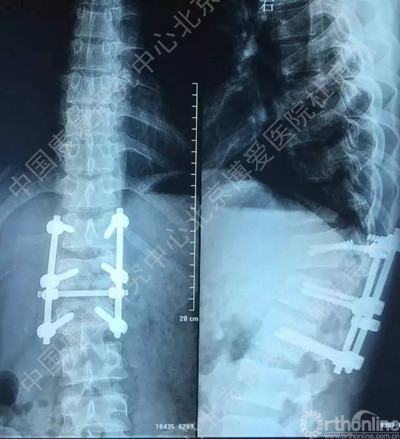

一月前干活时腰背部不慎被重约1吨重物砸伤,当时无意识障碍,无恶心、呕吐症状,自觉腰背部剧烈疼痛伴胸闷、憋气,双下肢失去知觉并不能活动,被送到当地医院救治,当时影像学检查示“腰1爆裂骨折伴脱位,腰1椎体附件骨折,腰2右侧横突骨折,胸12腰1之间侧方脱位,右侧第12肋椎关节脱位,右侧气胸,双肺挫伤,双侧胸腔积液”,经全面检查后诊断“胸12腰1骨折脱位,脊髓不全损伤,腰1椎体附件骨折,腰2右侧横突骨折,右侧第12肋椎关节脱位,右侧气胸,双肺挫伤,双侧胸腔积液等”。

伤后当天在全麻下行“后路探查减压复位椎弓根钉内固定植骨融合术”。手术后给予综合治疗,患者双下肢肌力较术前好转,但仍存在无力及感觉异常,大小便功能无明显改善。为进一步康复治疗及训练就诊中国康复研究中心北京博爱医院,以“腰椎骨折术后并脊髓损伤”收住院。患者近期精神、饮食、睡眠好,小便留置尿管,大便需借助开塞露。

3、胸12椎弓根钉断裂

柳申鹏 #1胸腰段椎体骨折脱位出现断钉原因:1.此处骨折脱位除椎体骨折外,附件及韧带等软组织损伤严重。从解刨上看3种因素决定此处是应力集中地。需固定到伤椎上下各2个椎体。2.从影像学可知,胸12腰1似乎过度撑开了。3.从影像学可知,极度不稳,应融合胸12腰1。下一步:去除断钉,延长上方固定到胸10或11并做后路截骨椎间隙植骨。或前路椎间隙植骨融合内固定